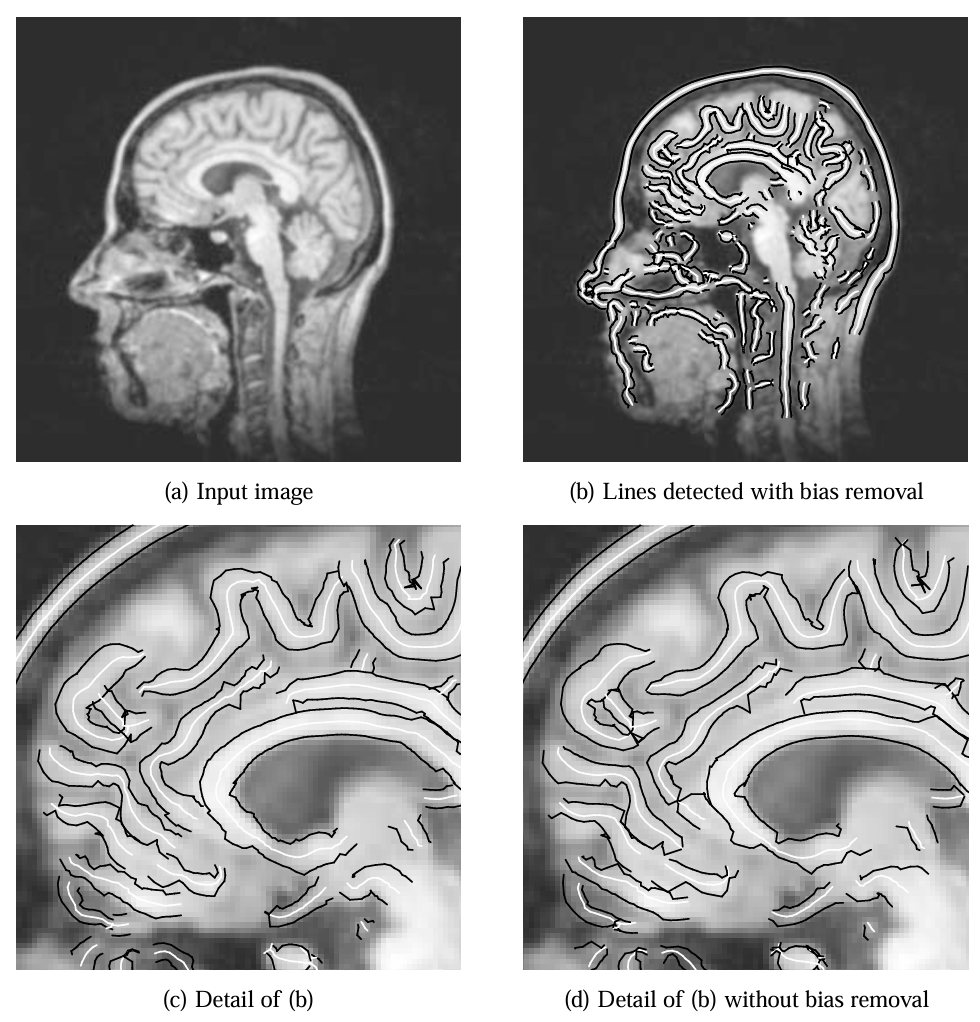

医学成像示例中,图 19(b) 的 MR 图像线条提取结果显示,颅骨和其他特征的位置与宽度精度较高,而未消除偏差的图 19(d) 在脑回区域因线条非对称性导致位置偏差。冠状动脉血管造影图 20 中,算法成功描绘血管狭窄区域,显示出在低对比度医学图像中的有效性。

图 19:在 MR 图像 (a) 中消除偏差后检测到的线条及其宽度 (b)。三倍放大细节 (c) 叠加在原始图像上。(d) 与未消除偏差的线条提取对比